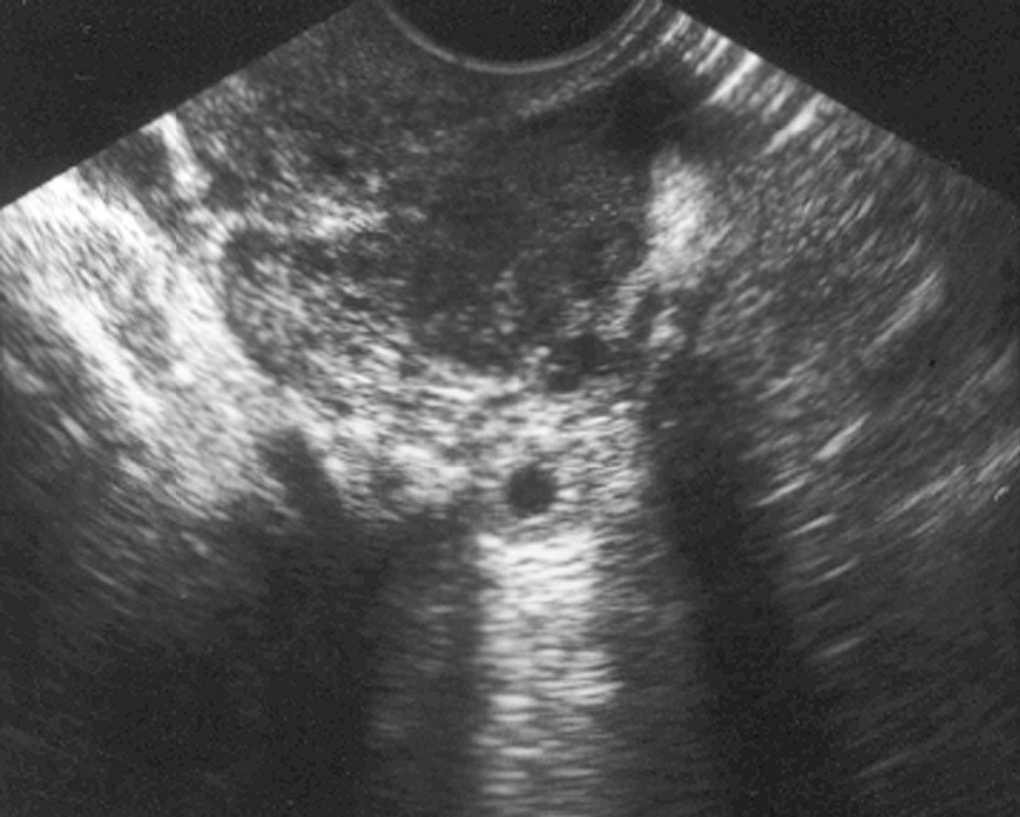

La ecografía transvaginal mostró un útero de características normales, con endometrio normal y una pequeña colección líquida en la cavidad (fig. 1). El ovario derecho era ecográficamente normal y, por debajo de él, aparecía una imagen redondeada hiperrefringente que rodeaba una zona central anecóica sugestiva de la presencia de un embarazo ectópico (fig. 2). El ovario izquierdo también era ecográficamente normal y, en íntimo contacto con él, se visualizaba una imagen similar a la descrita en el lado derecho (fig. 2).

Figura 1. Ecografía transvaginal.